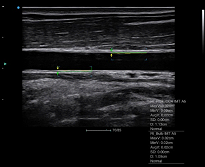

VS Flow

es una función en base al flujo Doppler de alta resolución espacial. Para identificar el cambio vectorial de las señales de Doppler del flujo sanguíneo. Se recoge un 30% más de señales laterales para mejorar la sensibilidad de todo el flujo, especialmente el flujo de velocidad lenta en los dedos y al riñón.

VS Flow mejora significativamente la sensibilidad y la resolución del flujo sanguíneo, lo que ayuda a los médicos a maximizar el valor de la aplicación clínica.